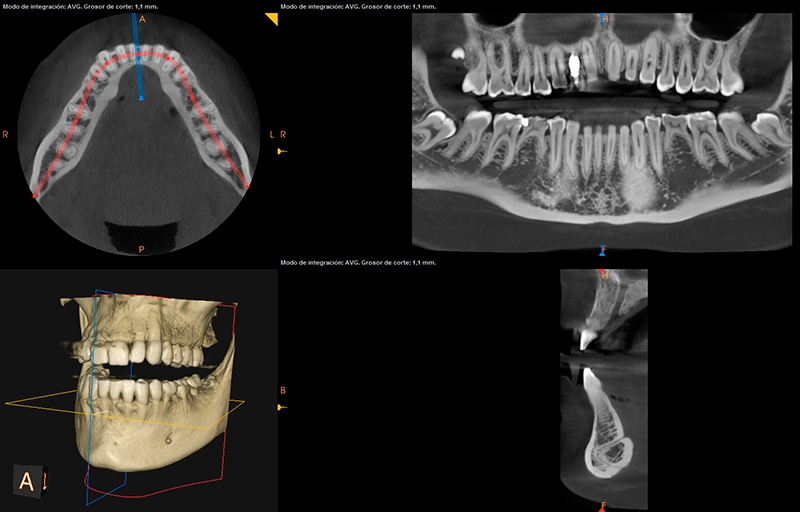

• TAC oral o radiografía en 3 dimensiones:

Clínica Dental Calatayudud, dispone de TAC dental de última generación en sus instalaciones para evitar desplazamientos innecesarios de nuestros pacientes. Así en una misma consulta se puede hacer un diagnóstico completo, incluyendo el tac si es necesario ya que es una herramienta muy valiosa para cirugía oral, implantes, endodoncia, periodoncia, etc.

Las tres dimensiones nos permiten ver con absoluta precisión y claridad cada una de las estructuras anatómicas de la cavidad oral. Por ejemplo, para la planificación de una cirugía de colocación de implantes, este sistema de diagnóstico nos permitirá determinar el volumen óseo (tanto en altura como en anchura), la proximidad a otras estructuras anatómicas…